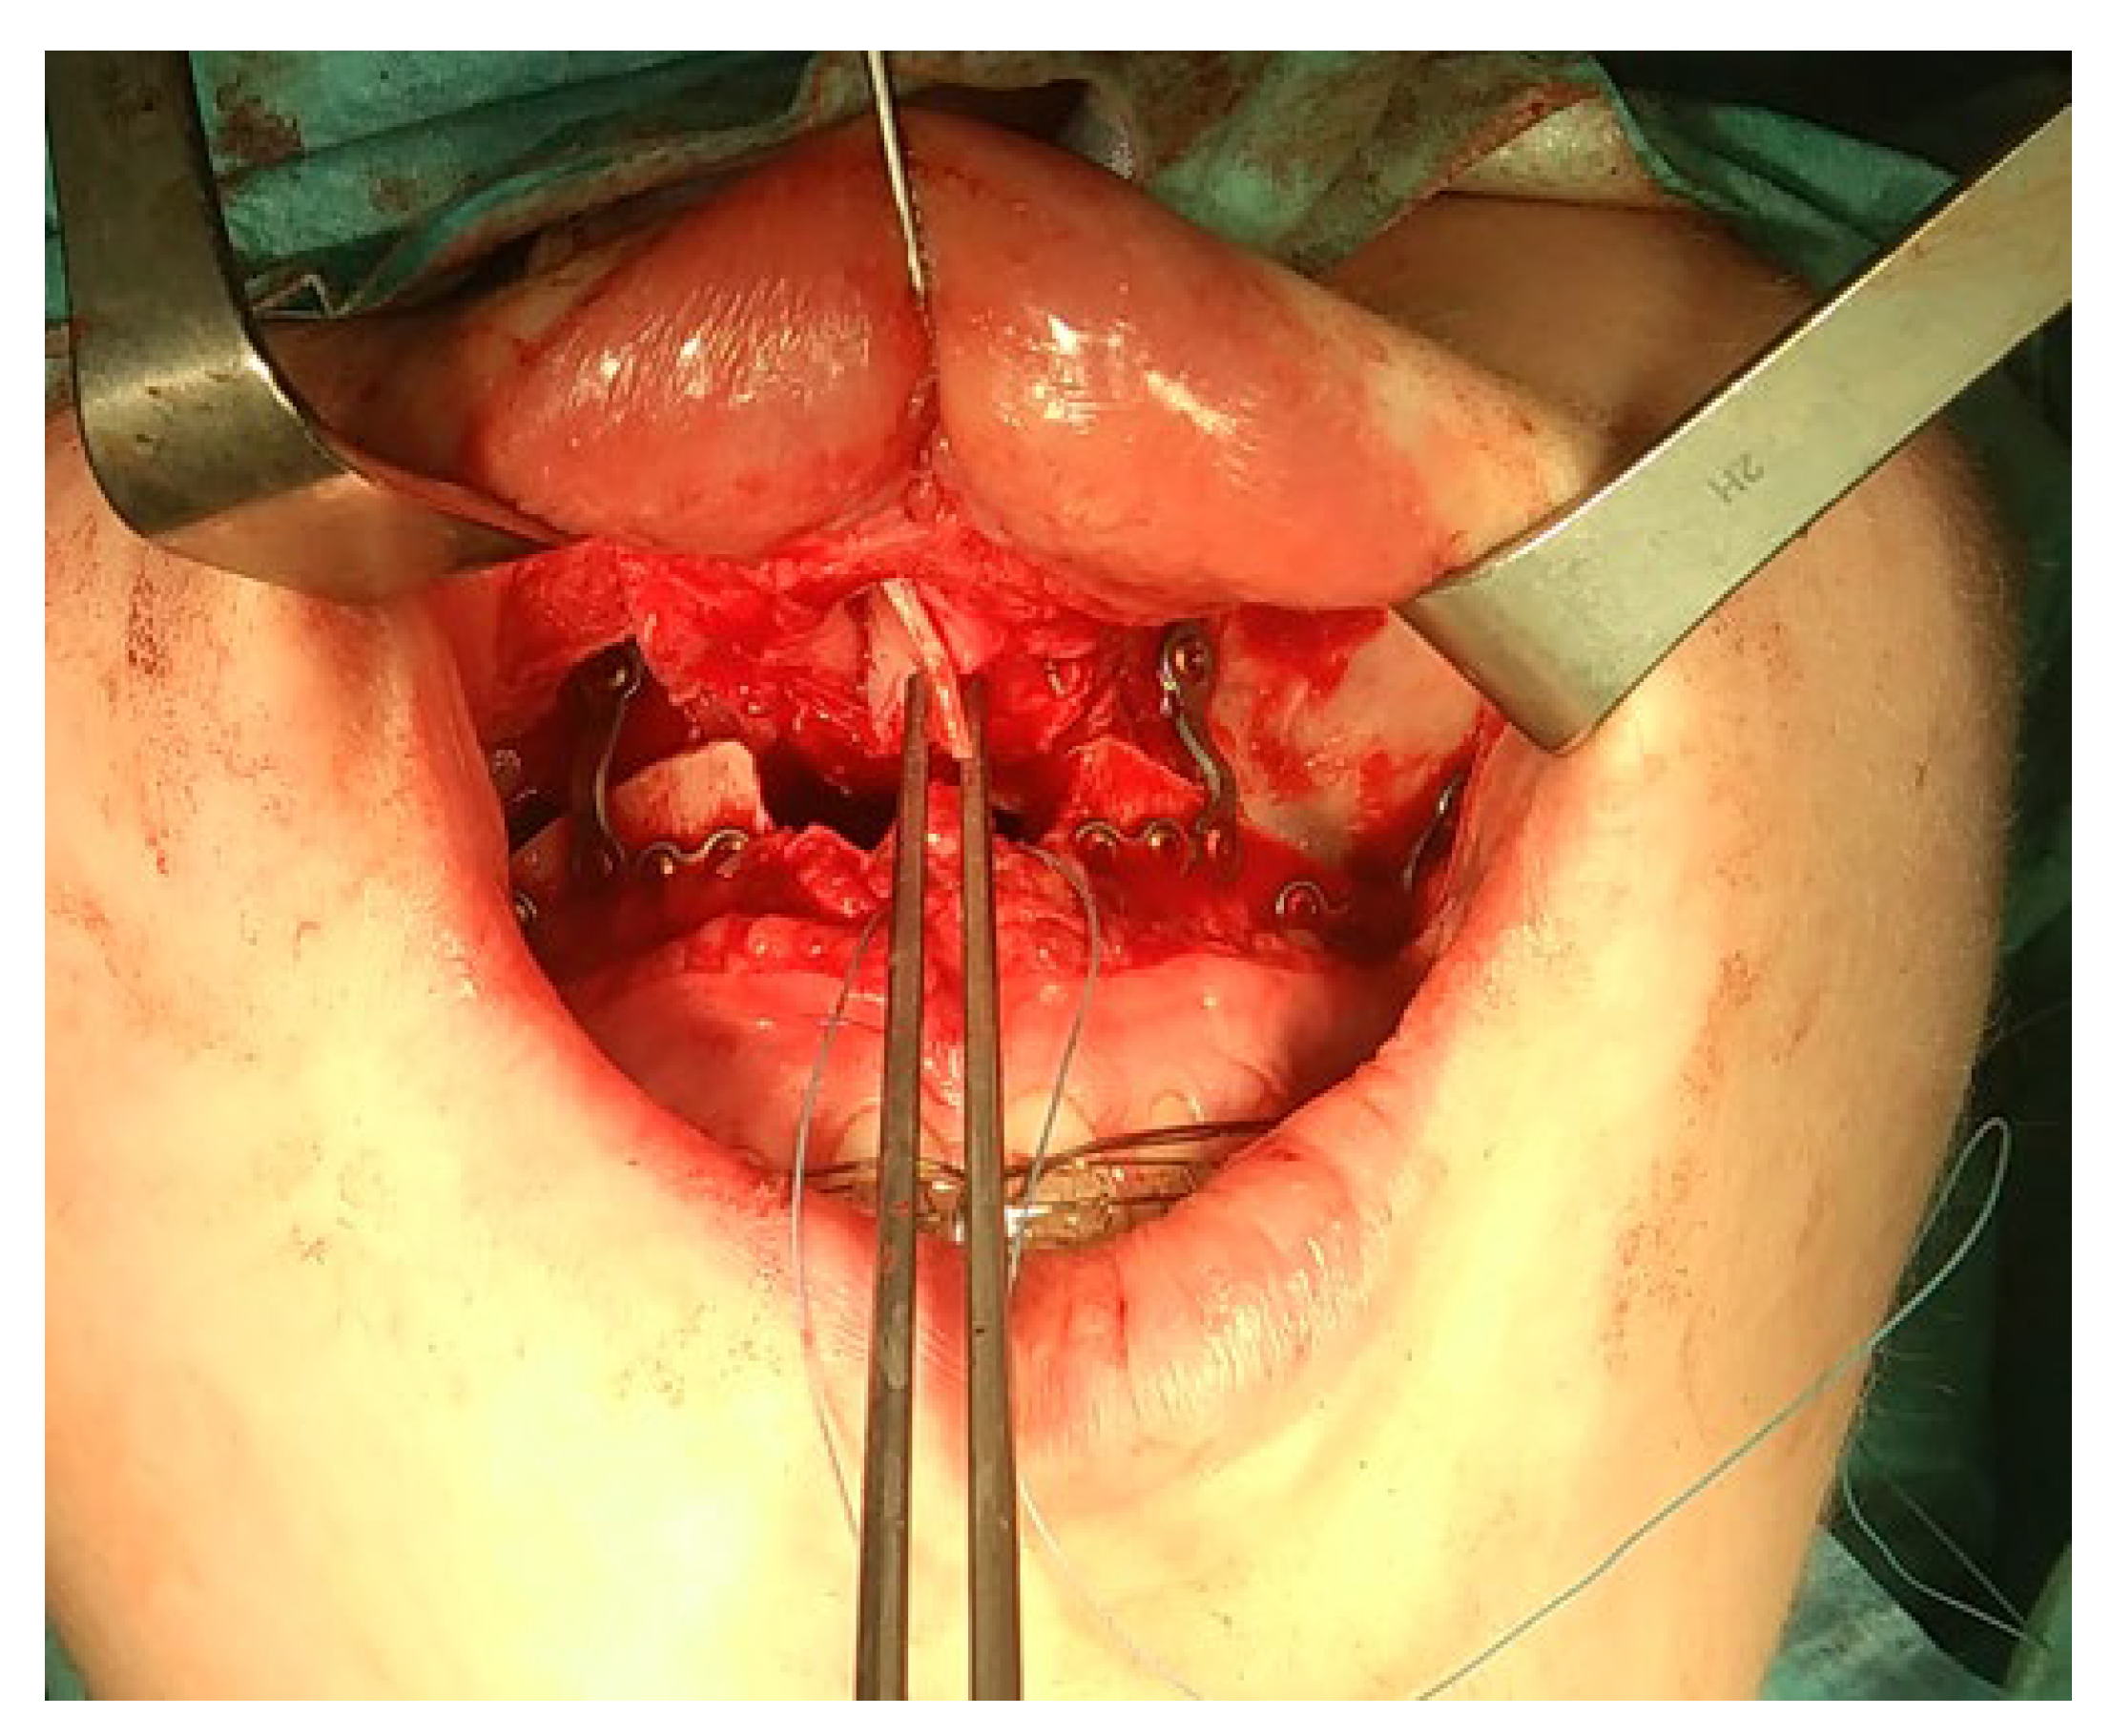

- Transoral approach. This might include techniques with mandibular coronoid process osteotomy to gain more visibility toward the condyle, as reported by Choung et al. [95]. A similar approach to the intraoral approach was described by Wang et al., which might be combined with coronoid process resection and an IVRO procedure–intraoral vertical ramus osteotomy [96,97]. Approaches with computer-guided/3D navigation techniques can also be useful. The intraoral approach for a condylectomy is challenging and can be used in various technique alternations. Some authors combine it with a coronoidectomy, while others combine it with temporal coronoid process osteosynthesis to improve access to the MC. The presented method by Deng et al. described new insights into accurate and safe intraoral approaches [98]. The endoscopic-assisted transoral approach is a similar approach and technique used for intraoral condyle fracture osteosynthesis after fractures and can also be used with a great deal of success to improve intraoral condylectomy [99,100,101].